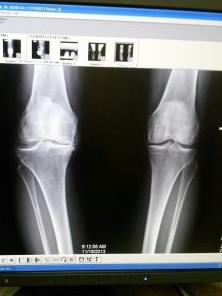

Before surgery:

At this point I had so much genu varus “bowed” on my right leg. I was starting to fear that I would tear my LCL ligament it was so deformed. I began wearing an unloader brace to offset this for when I played tennis or any kind of activity.